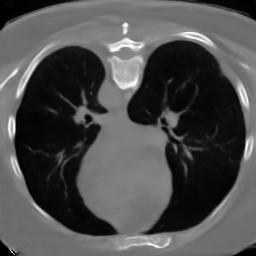

We demonstrate our model’s performance on two publicly available datasets: BraTS 2023 Adult Glioma [1, 2, 15, 20] and LIDC-IDRI [14]. For training on the BraTS dataset, we use the T1-weighted brain MR-images, clip the upper and lower 0.1 percentile intensity values, zero pad the volumes to a size of and normalize them to a range of . For training on the LIDC-IDRI lung CT dataset, we initially clip all values below and the upper 0.1 percentile intensity values. We then resample the images to an isotropic voxel size of 1 , center crop them to a size of , and normalize to a range of . When training on images with a resolution of , we perform downsampling by applying average pooling.

The results presented in Table 1 and 2 show our proposed method’s performance on unconditional 3D brain MR and chest CT image generation. Our proposed approach not only outperforms most comparing methods in FID and MS-SSIM metrics, it also has the lowest inference GPU memory footprint at a resolution of and was the only diffusion-based method that could be trained at a resolution of . Operating in the wavelet domain and profiting from the reduced spatial dimension also results in a relatively short inference time of / at the respective resolutions. Compared to the results presented in [23], we did not find that incorporating wavelet information into the network’s feature space (WavU-Net) increased the model’s performance. Qualitative results of our proposed method (WDM) are shown in Fig. 2 and 3. A qualitative comparison of samples produced by all evaluated methods can be found in the Supplementary Material.